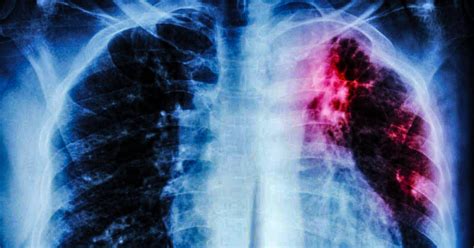

Pulmonary tuberculosis coexist with lung cancer: case ...

Pulmonary tuberculosis coexist with lung cancer: case ... from ajbm.net